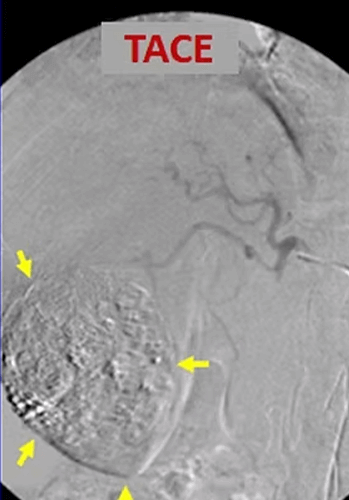

In our patient who has a large (10cm) HCC (arrows) in the liver, the control computed tomography after Lipiodol-TACE shows that the tumor has lost its viability and its diameter decreased to 4 cm.